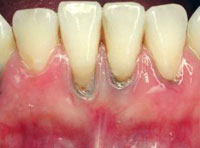

Gum disease develops gradually and can be categorized into different stages depending on its severity.

• Gingivitis: Early stage with inflammation and bleeding gums

• Periodontitis: Advanced stage affecting supporting bone and tissues

• Scaling and root planing: Deep cleaning below the gum line